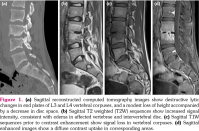

Lumbar vertebral computed tomography revealed a decrease in the right half of the disc height at the L3-4 intervertebral disc level (Figure 1a). Lumbosacral spinal magnetic resonance imaging (MRI) revealed in sagittal T2A sequences increased signal intensity, consistent with edema in the affected vertebrae and intervertebral disc (Figure 1b). The sagittal T1A sequences prior to contrast enhancement showed signal loss in the vertebral corpuses (Figure 1c), while sagittal postcontrast images showed a diffuse contrast uptake in the corresponding areas (Figure 1d). The axial postcontrast images showed involvement of the right paravertebral and foraminal soft tissues, and increased signal intensity consistent with the involvement of the right L3 nerve (Figure 2). Radiological findings were consistent with spondylodiscitis.

The patient was placed on steroid therapy, and a good response was achieved in terms of clinical and laboratory findings. Figures 1 and 5 present the MRI findings at baseline and during follow-up. Thus, early diagnosis provided good response to disease without organ damage.